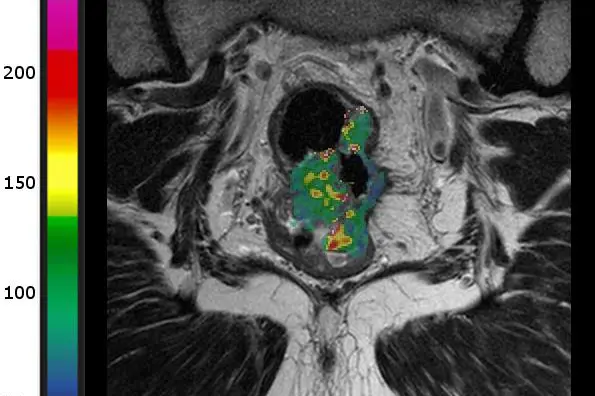

Her er MR-bilder av to ulike pasienter som har endetarmskreft i samme stadium. Den øverste har lav blodgjennomstrømning, og den nederste har høy. Den første ble diagnostisert med spredning til lever etter 12 måneder, mens den andre er sykdomsfri etter fem år. Kilde: Bakke et al. Radiology 2020